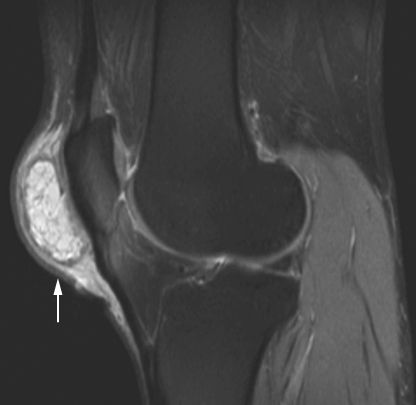

Возникает при вытекании синовиальной жидкости в подколенную ямку, в результате чего образуется капсула, наполненная жидкостью. Размеры кисты могут быть разными, достигая порою размеров кулака. Наполненная жидкостью киста легко пальпируется.